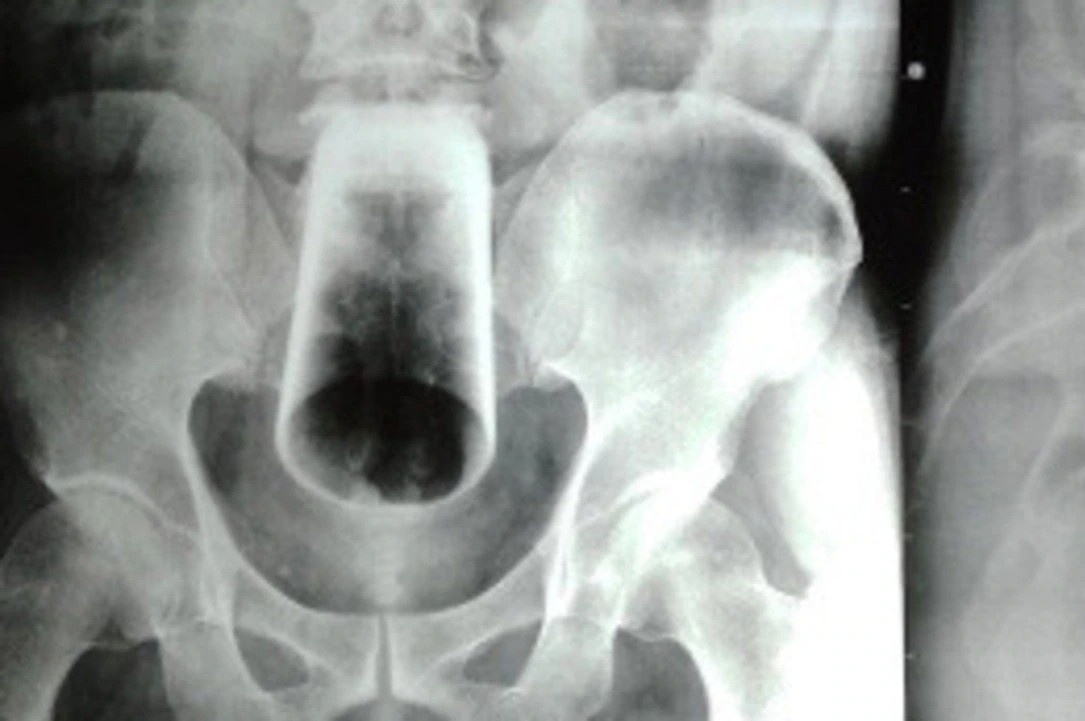

Bệnh nhân bị đa chấn thương nghiêm trọng do bị xe tải cán. Ảnh: Duy Hiệu.

Kết quả kiểm tra tại Bệnh viện Đa khoa Thống Nhất cho thấy bệnh nhân bị gãy vỡ phức tạp vùng khung chậu, cụt bên trái, chấn thương bàng quang, bụng kín và dập nát vùng tầng sinh môn, bẹn đùi phải.

Sau khi hội chẩn, các bác sĩ chuẩn bị lượng lớn máu để bắt đầu phẫu thuật cho bệnh nhân. Trong quá trình phẫu thuật, bệnh nhân được cố định khung chậu, mở hậu môn nhân tạo, cắt lọc phần dập nát ở tầng sinh môn, vùng mông và đùi phải.